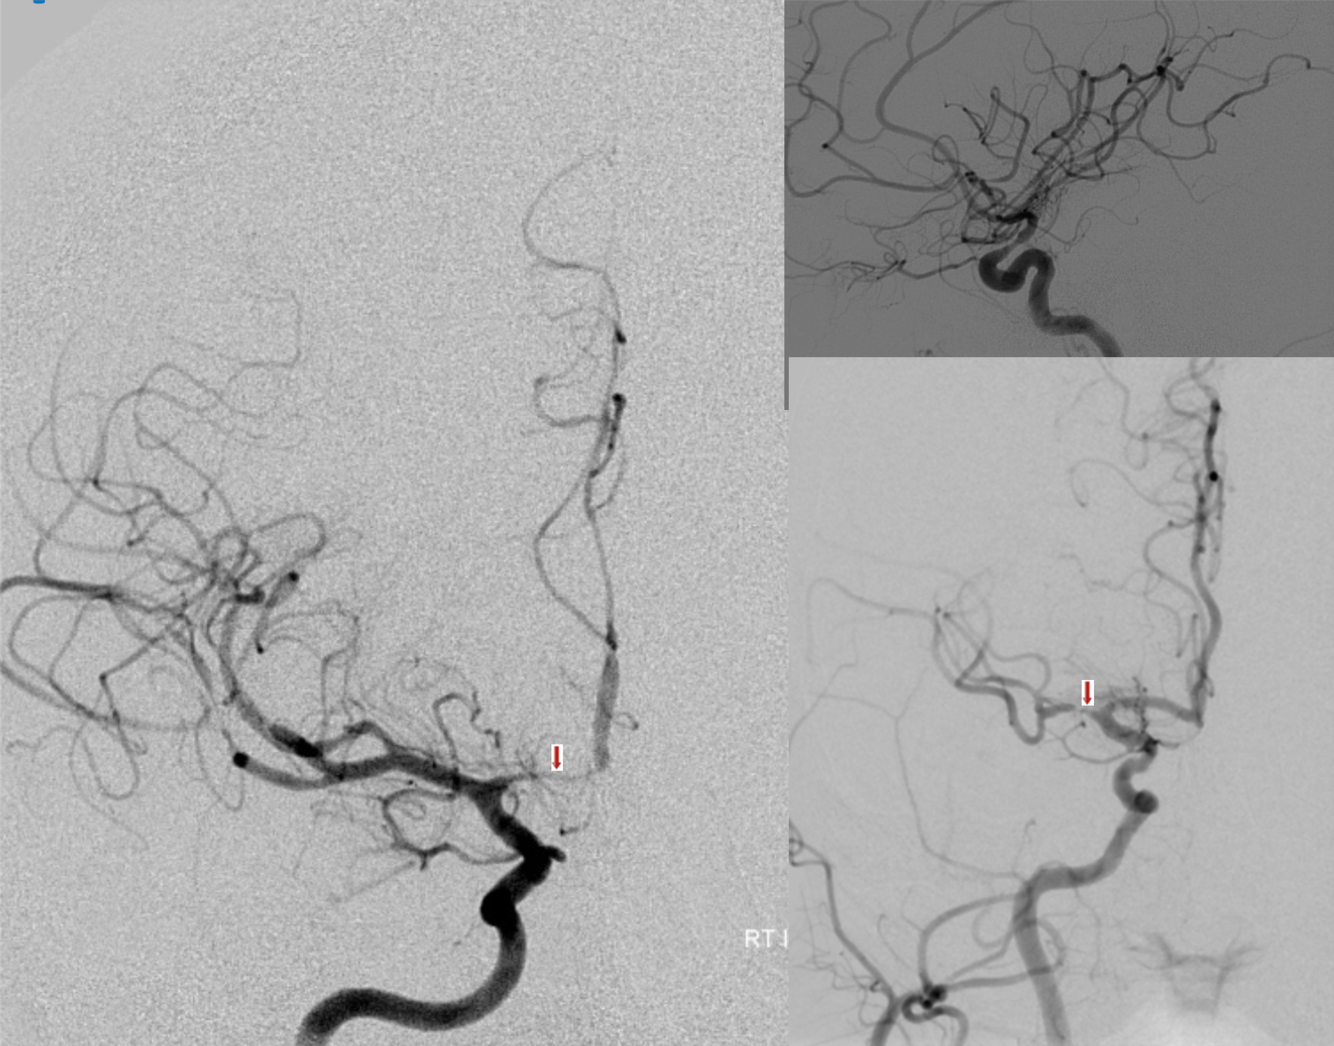

Angiograms after subarachnoid hemorrhage in different patients.

Vasospasm